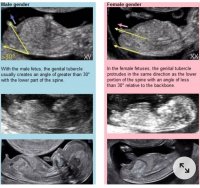

Nub teorien går ut på å gjette kjønnet ut i fra vinkelen "nuben" står i. Gutte-nub står mer opp og gjør det allerede fra uke 11-12. Jente-nub ligger mer flatt ned.